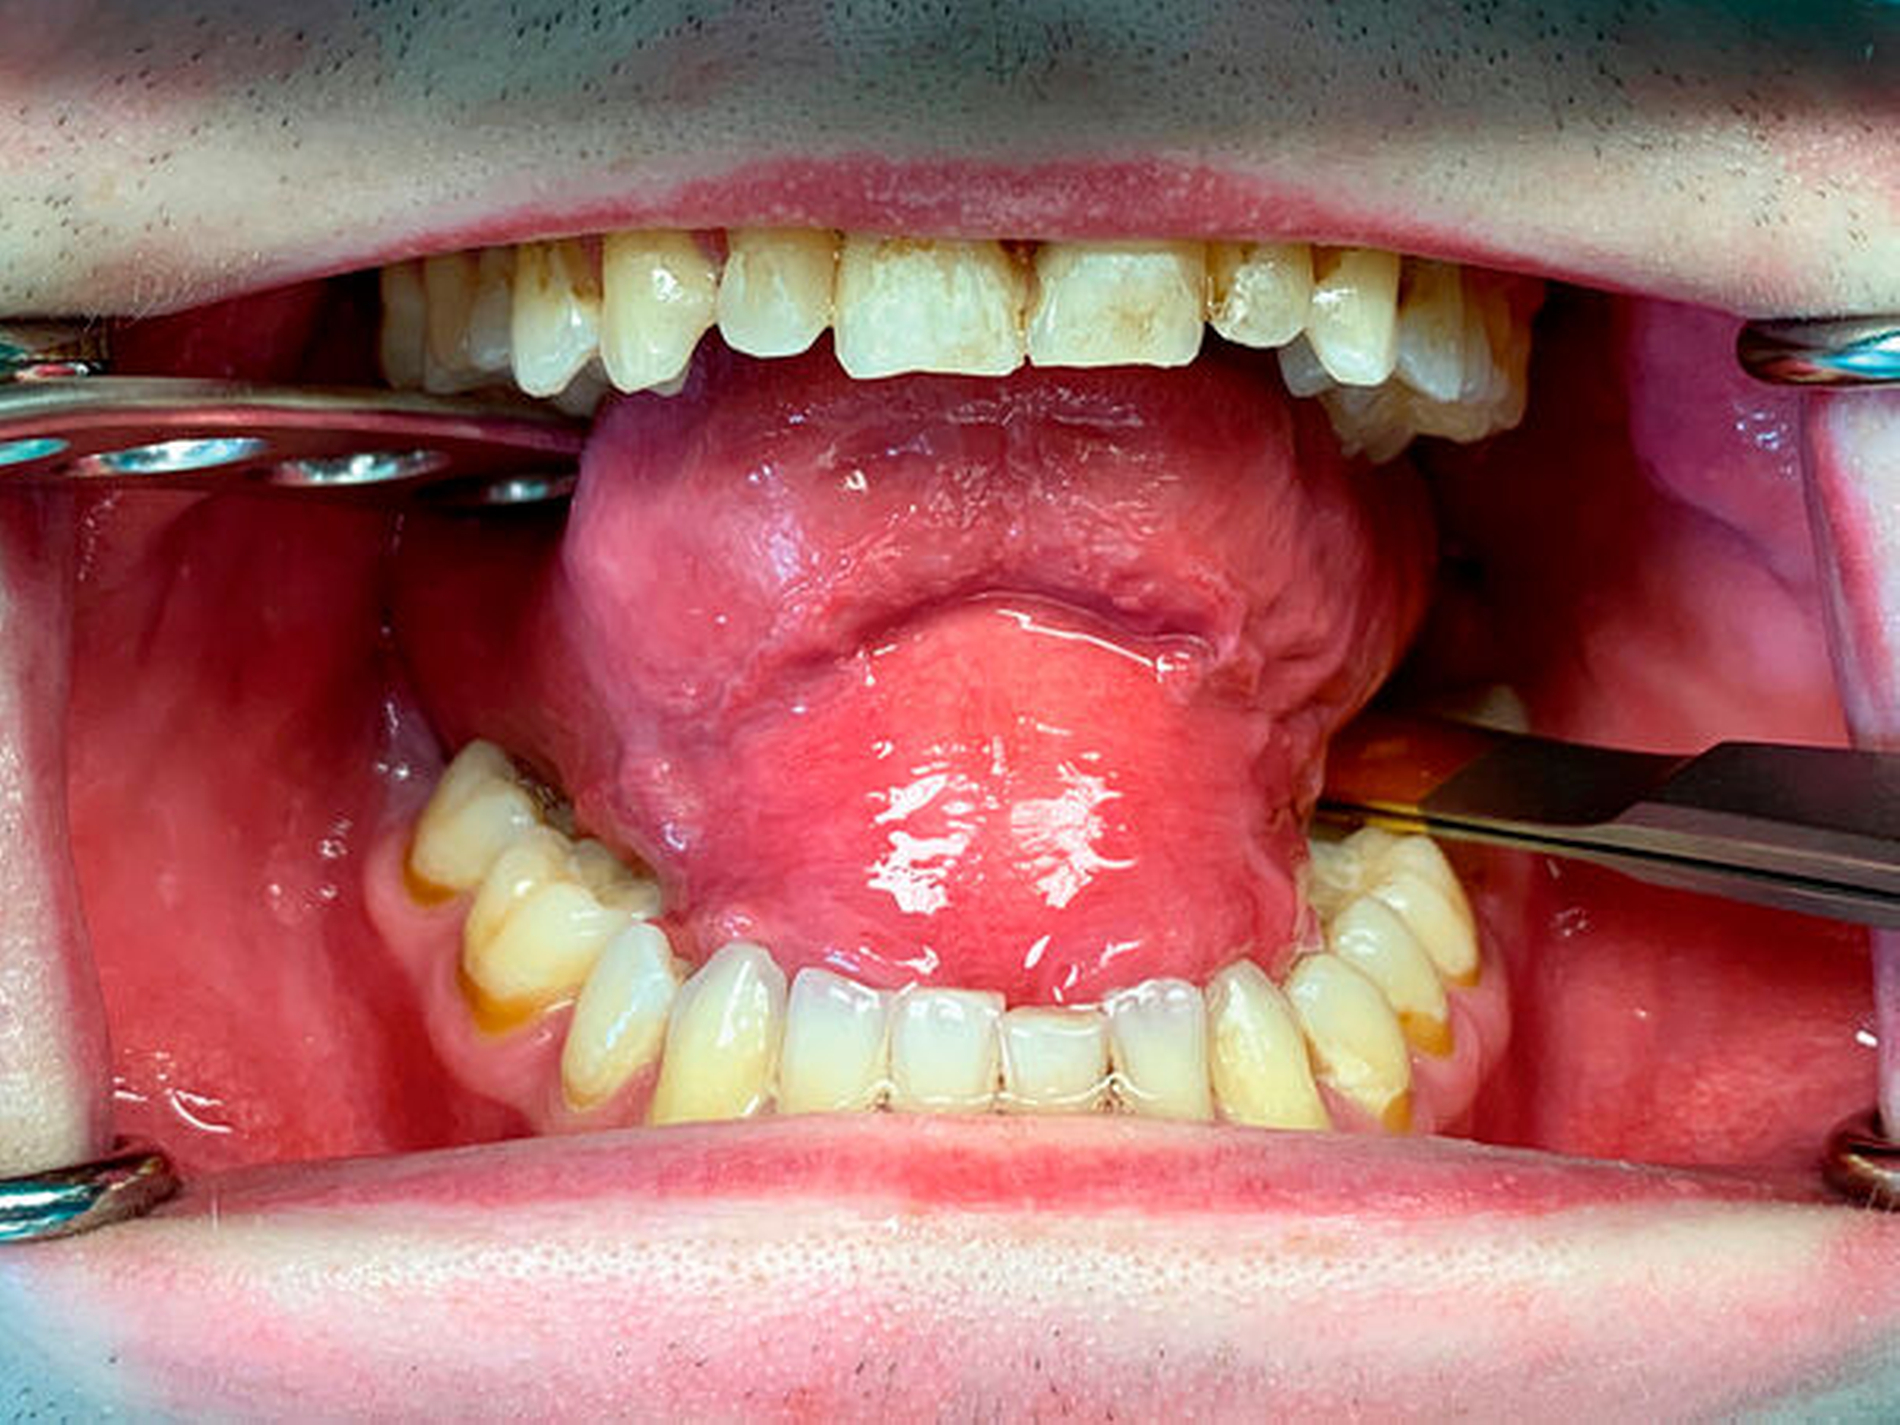

Bei der klinischen Untersuchung zeigte sich eine mäßig ausgeprägte, weiche, schmerzlose submentale Schwellung. Die Haut im Bereich des Kinns war unauffällig. Klinisch bestand keine Vergrößerung der regionalen Lymphknoten oder der Speicheldrüsen (Abbildung 1). Intraoral stellte sich eine deutlich ausgeprägte, weiche Schwellung des Mundbodens mit deutlicher Verdrängung des Zungenkörpers nach palatinal dar. Die Mundschleimhaut war ansonsten unauffällig. Die Speichelsekretion, insbesondere der Glandula submandibularis beidseits, war regelrecht. Außer einem sanierungsbedürftigen Gebiss bei schlechter Mundhygiene waren keine Auffälligkeiten festzustellen (Abbildung 2).